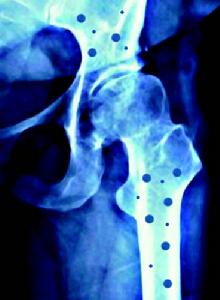

關節X線檢查:早期示軟組織腫脹,骨質疏鬆後期廣泛新骨形成,關節腔變狹,邊緣骨質破壞和骨質硬化症等改變。早期病理改變類似膿皰性銀屑病。可見表皮角化過度角化不全,表皮嵴延長,表皮內有許多白細胞浸潤,形成海綿狀膿皰。角質層明顯增厚,含有角化不全細胞和固縮的中性粒細胞核。真皮內有大量中性粒細胞浸潤。